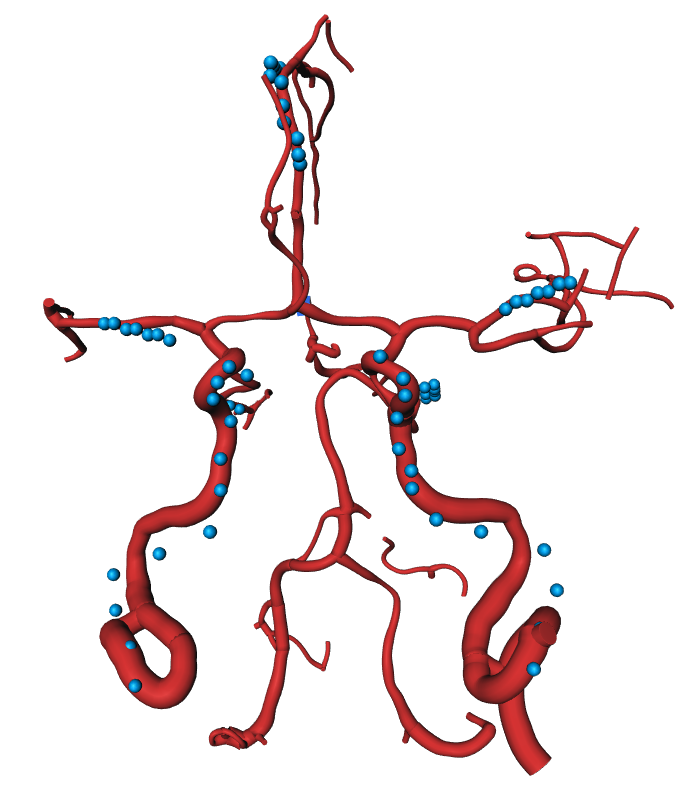

Refer to caption

Figure 3: The surface model of the vessel tree of two patients demonstrating the vein suppression feature on different rendering distances. The upper row is an example of a patient with no LVO present. Contrary to the lower row, where the patient suffers an LVO on the left MCA branch. The expansion on the far right shows the full vessel tree including all veins. Relevant structures close to the Circle of Willis are visually obstructed.

4.2.2 Vein Suppression

In some cases, for instance if large contrast boluses were injected, veins like the sinus sagittalis may disturb the visual impression. The second search node property enables an easy way of displaying only relevant parts by placing the root node into the Circle of Willis and visualizing only nodes and their paths accessible within a certain geodesic distance. Fig. 3 shows two trees on different geodesic distances. The lower tree is from a patient who suffers an LVO on the left MCA branch, while the top one is LVO negative, showing no noticeable defects. As displayed, veins and more distant vessels may conceal stroke-relevant parts in their full representation on the right end and disappear towards the left side while the distance is decreased.